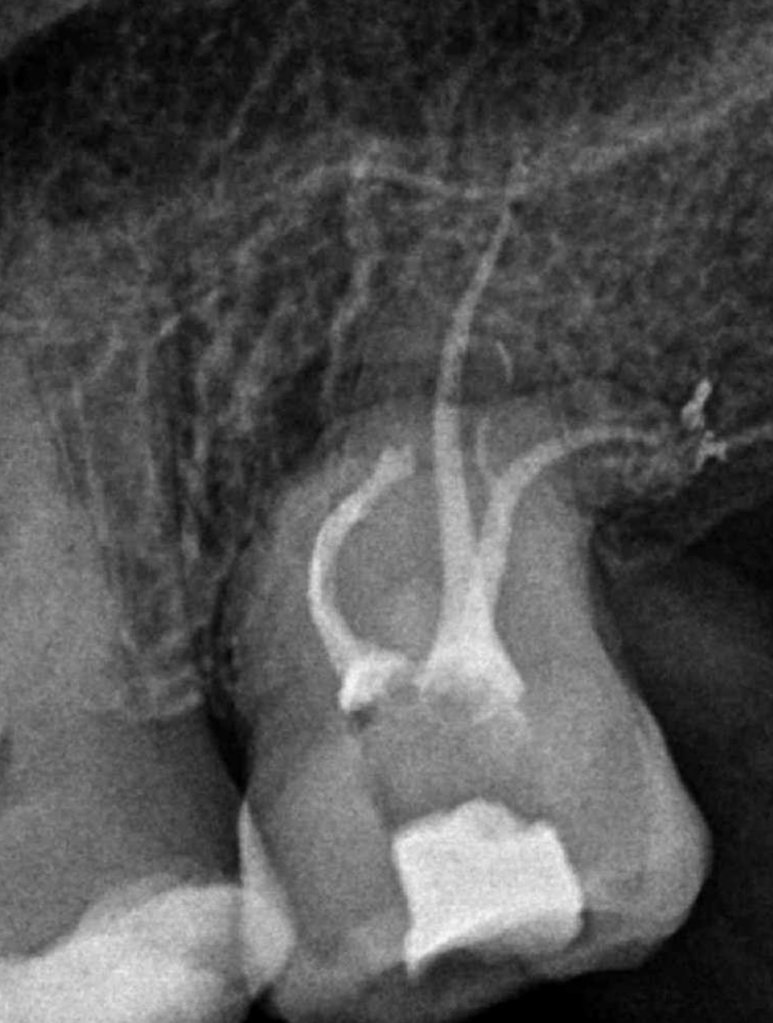

Reco preendo + 4 conductos molar superior